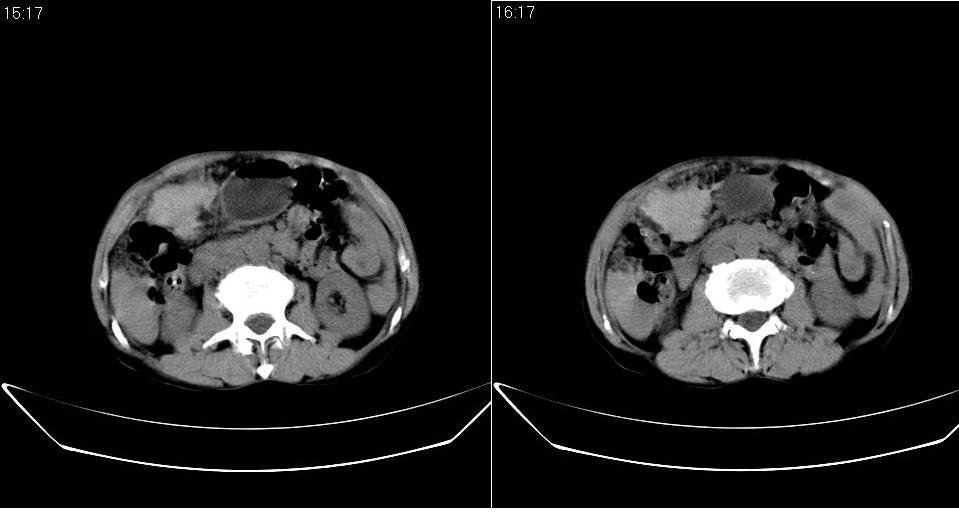

标题: CT20033:上腹部CT平扫

男 66岁,腹疼,b超提示考虑肝癌。

考虑巨块型型肝癌坏死、出血。建议增强。

考虑巨块型型肝癌,建议行进一步检查,如增强、afp检查。

没完善检查手段,增强后再说,就算你有一万个理由说是肝癌,证据何在?

呼吁从事ct诊断的同志们,腹部占位,特别是肝脏病变没有平扫和三期增强检查,我们底气不足,拿什么来让临床医师信服我们。